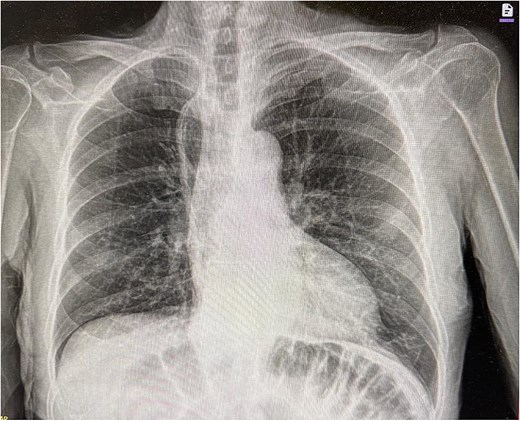

Upon arrival at the ED, the patient was afebrile and hemodynamically stable. Initial labs showed WBC 10.19, H/H 13.2/41.3, platelets 419, Na 136, K 5.3, creatinine 1.0. Portable X-ray and computed tomography (CT) imaging revealed small bowel obstruction secondary to herniation of the small bowel into the right hemithorax through a recurrent hiatal hernia (Figs 1 and 2).

Chest X-ray showing compressed lung and fluid due to herniated small bowel.